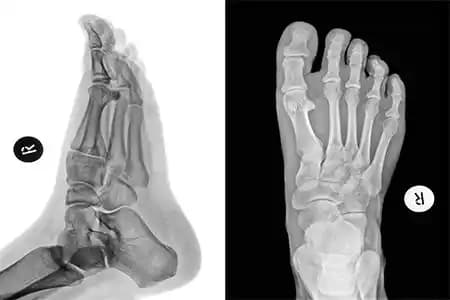

Röntgen: Kemiğin durumunu net görmek için temel görüntüleme yöntemidir.

Tarak kemiği kırığı, ayakta bulunan beş adet ince ve uzun kemikten oluşan metatars kemiklerinden birinin ya da birkaçının kırılması durumudur. Bu kırık türü, özellikle aktif yaşam süren bireylerde sıkça görülür ve doğru müdahale edilmediğinde yürüyüş ve denge problemlerine yol açabilir. Ayak sağlığının korunması ve estetik görünümün devamı için tarak kemiği kırıklarının erken teşhisi ve uygun tedavisi büyük önem taşır.